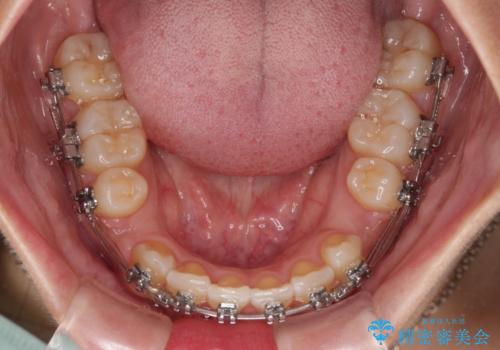

- 矯正装置

- メタルブラケット

- 治療期間

- 3年5ヶ月

上顎小臼歯の歯根が左右ともに大きく曲がっており、スペースクローズに時間がかかってしまいました。